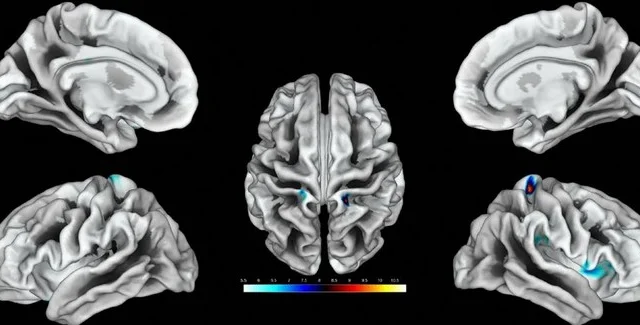

Ділянки мозку, що відповідають за клітор, виділені кольором. | Фото: ScienceAlert

Дослідники виявили ділянки мозку, які відповідають за реакцію на дотик до геніталій жінок. Виявилося, що вони розвиненіші в тих, хто займається сексом частіше.

Під час дослідження проводилася стимуляція клітора 20 дорослих жінок, під час якої сканування мозку здійснювалося за допомогою функціональної магнітно-резонансної томографії. Ученим вперше вдалося нанести на карту ділянки мозку, які відповідають за реакцію на дотик до геніталій у жінок. За словами дослідників, ці результати можна використовувати для лікування жінок, які страждають від сексуальної дисфункції, повідомляє ScienceAlert.

Соматосенсорна кора головного мозку отримує та обробляє інформацію про відчуття, що виходить з усього тіла. Кожна частина тіла відповідає окремій ділянці кори головного мозку та утворює репрезентативну карту. Але досі було незрозуміло, які ділянки відповідають за жіночі геніталії.

Стимулювання клітора відбувалося 8 разів поспіль протягом 10 секунд з 10-секундними перервами. У результаті сканування ділянок мозку вчені визначили, які саме з них відповідають за жіночі геніталії. Також учені з'ясували, що у жінок, які мають частіші сексуальні контакти, ці ділянки збільшені в розмірах.

"Ми виявили зв'язок між частотою статевого акту і товщиною окремих, нанесених на карту ділянок. Чим більше сексу, тим більша ця ділянка", — говорить Хайм.